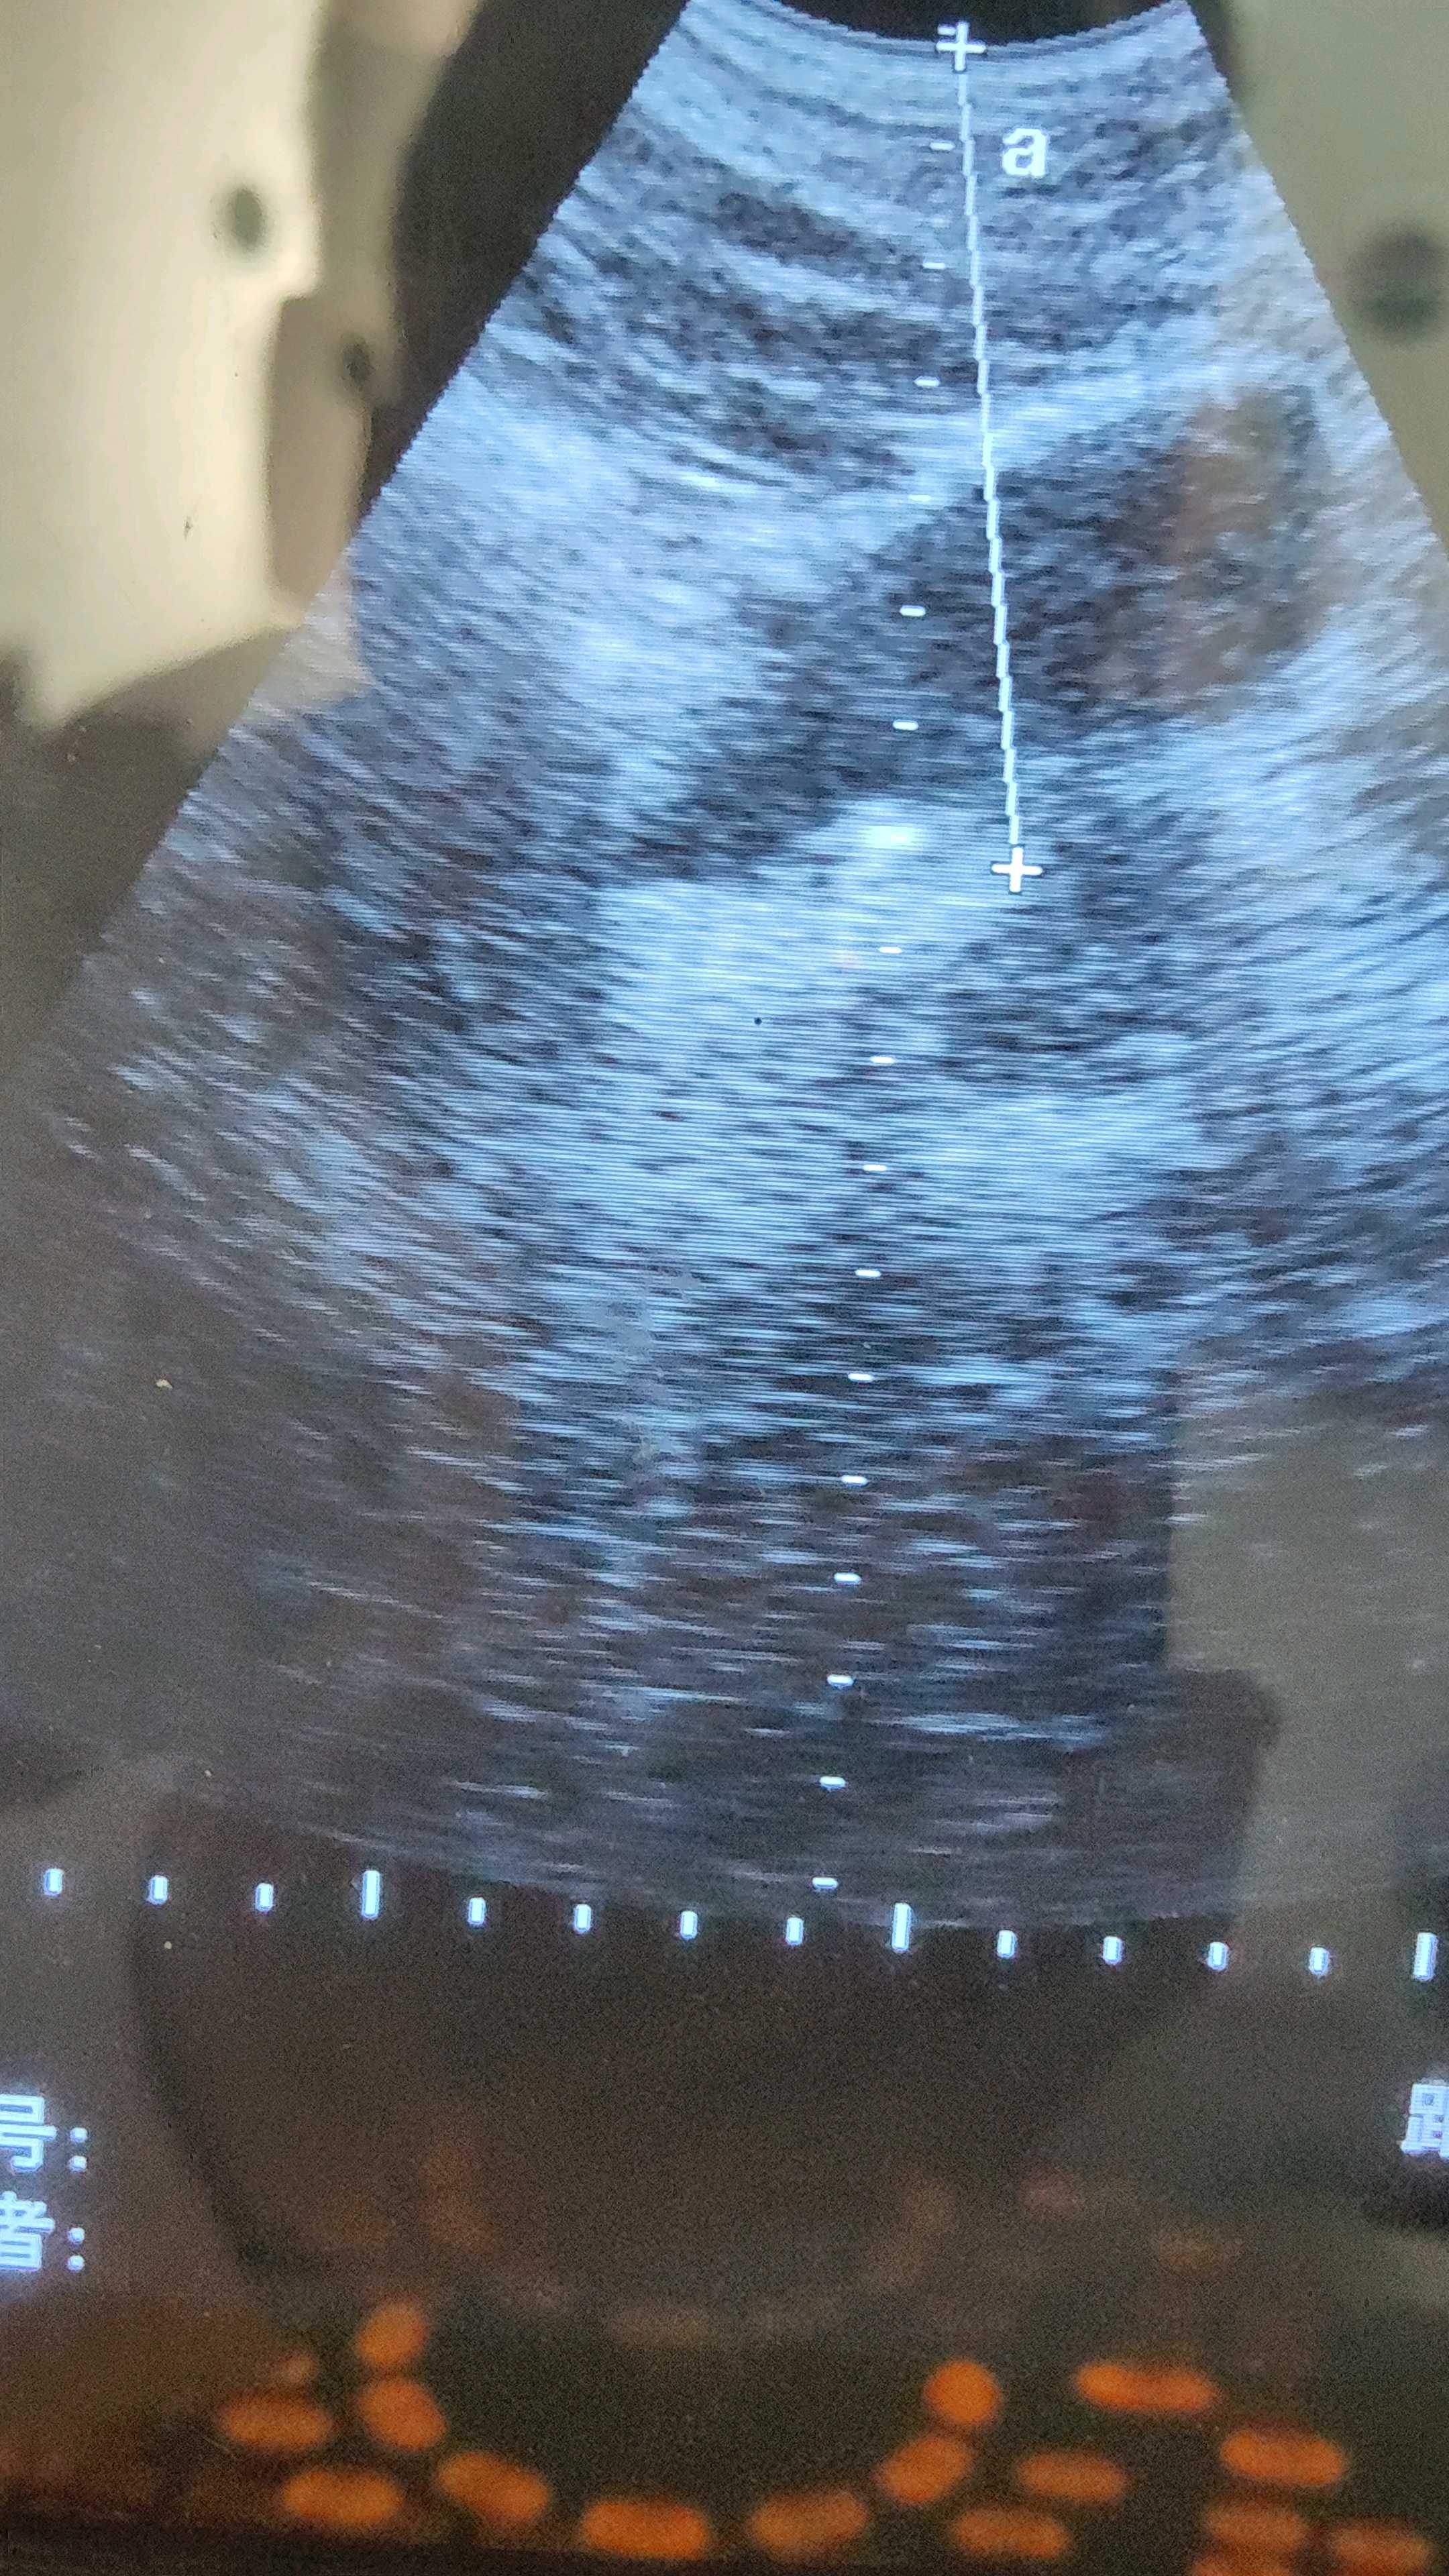

这是一例右输尿管末端结石体外冲击波碎石,拍的不好。

舞蹈征、落雪征就是结石收到冲击波作用震动和结石碎屑散落的征象,只有有扩展空间的有水环境的才能看到,俯卧位时容易看到,输尿管结石肾结石不容易看到